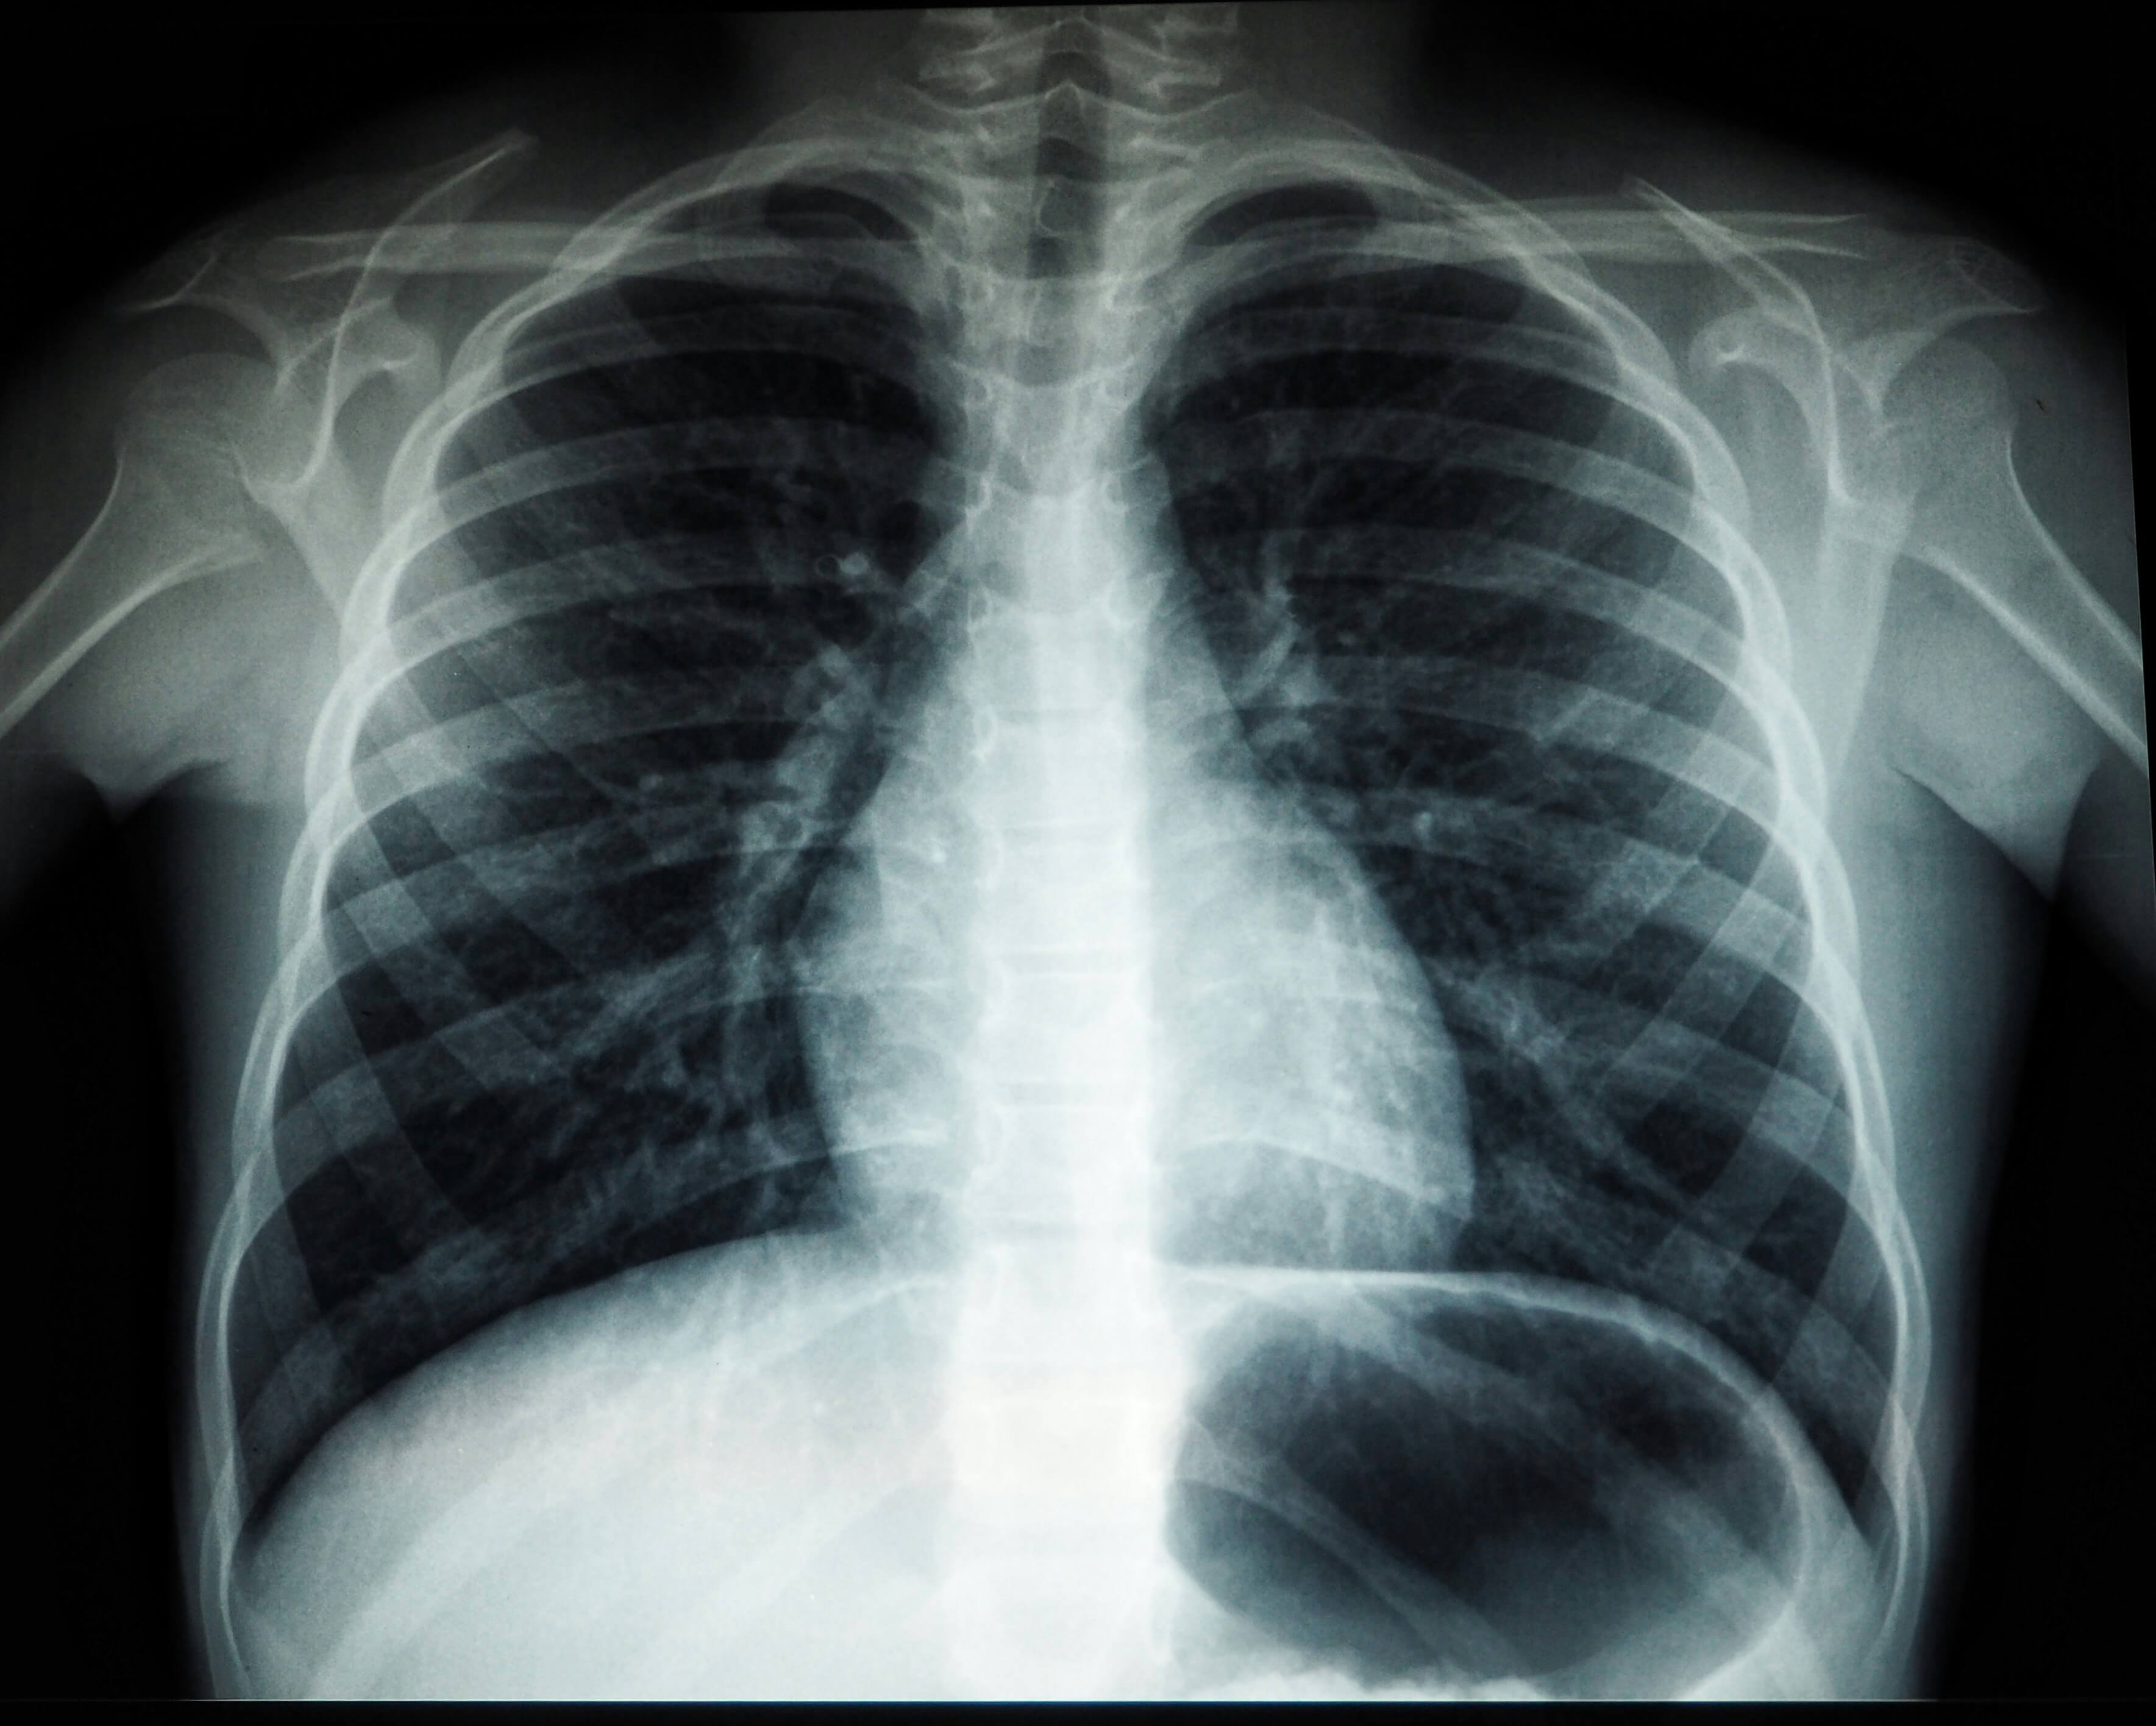

2. 가래에 피가 섞여 나옴(객혈) 🩸

기침을 할 때 가래에 피가 묻어나거나 붉은색 점액이 섞여 나온다면 폐암 초기 증상일 가능성이 있습니다.

이는 폐의 혈관이 손상되거나, 종양이 기관지 점막을 자극하면서 출혈이 발생하기 때문입니다.

가래의 색이 붉은색, 갈색, 녹슨 색과 비슷하다면 폐 내부에 출혈이 있는 것일 수 있으므로 신속한 검진이 필요합니다.

단순한 기관지염이나 폐렴에서도 피 섞인 가래가 나올 수 있지만, 특별한 이유 없이 반복적으로 이러한 증상이 나타난다면 반드시 의사의 진료를 받아야 합니다.